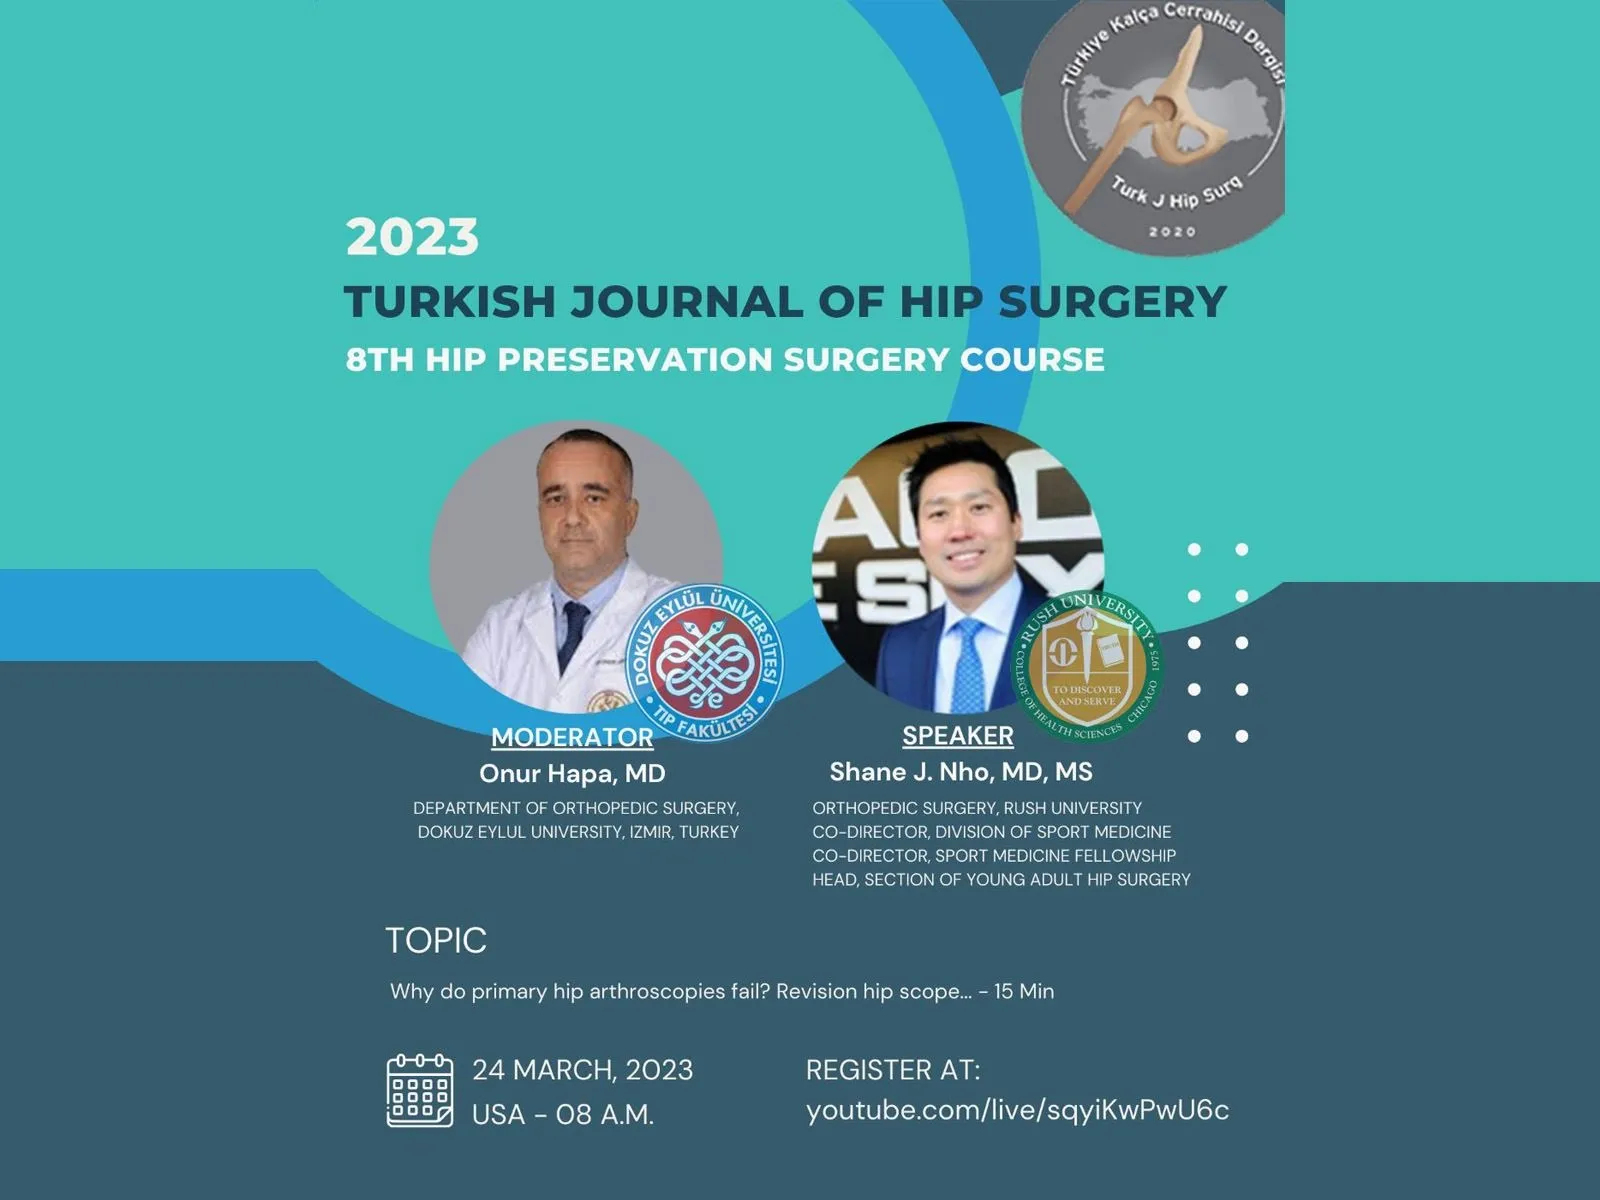

2023 TURKISH JOURNAL OF HIP SURGERY 8TH HIP PRESERVATION SURGERY COURSE

Simultaneous hip arthroscopy and peri-acetabular osteotomy; When? How? - 15 Min Questions and Discussion - 10 Min